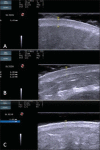

The present essay is aimed at getting the radiologist familiar with the basic histological skin structure, allowing for a better correlation with sonographic findings. A high-frequency (22 MHz) ultrasonography apparatus was utilized in the present study. The histological analysis was performed after the skin specimens fixation with formalin, inclusion in paraffin blocks and subsequent staining with hematoxylin-eosin. The authors present a literature review showing the relationship between sonographic and histological findings in normal cutaneous tissue, and discuss the technique for a better performance of the sonographic scan. High-frequency ultrasonography is an excellent tool for the diagnosis of different skin conditions. However, as this method is operator-dependent, it is crucial to understand the normal skin structure as well as the correlation between histological and sonographic findings.